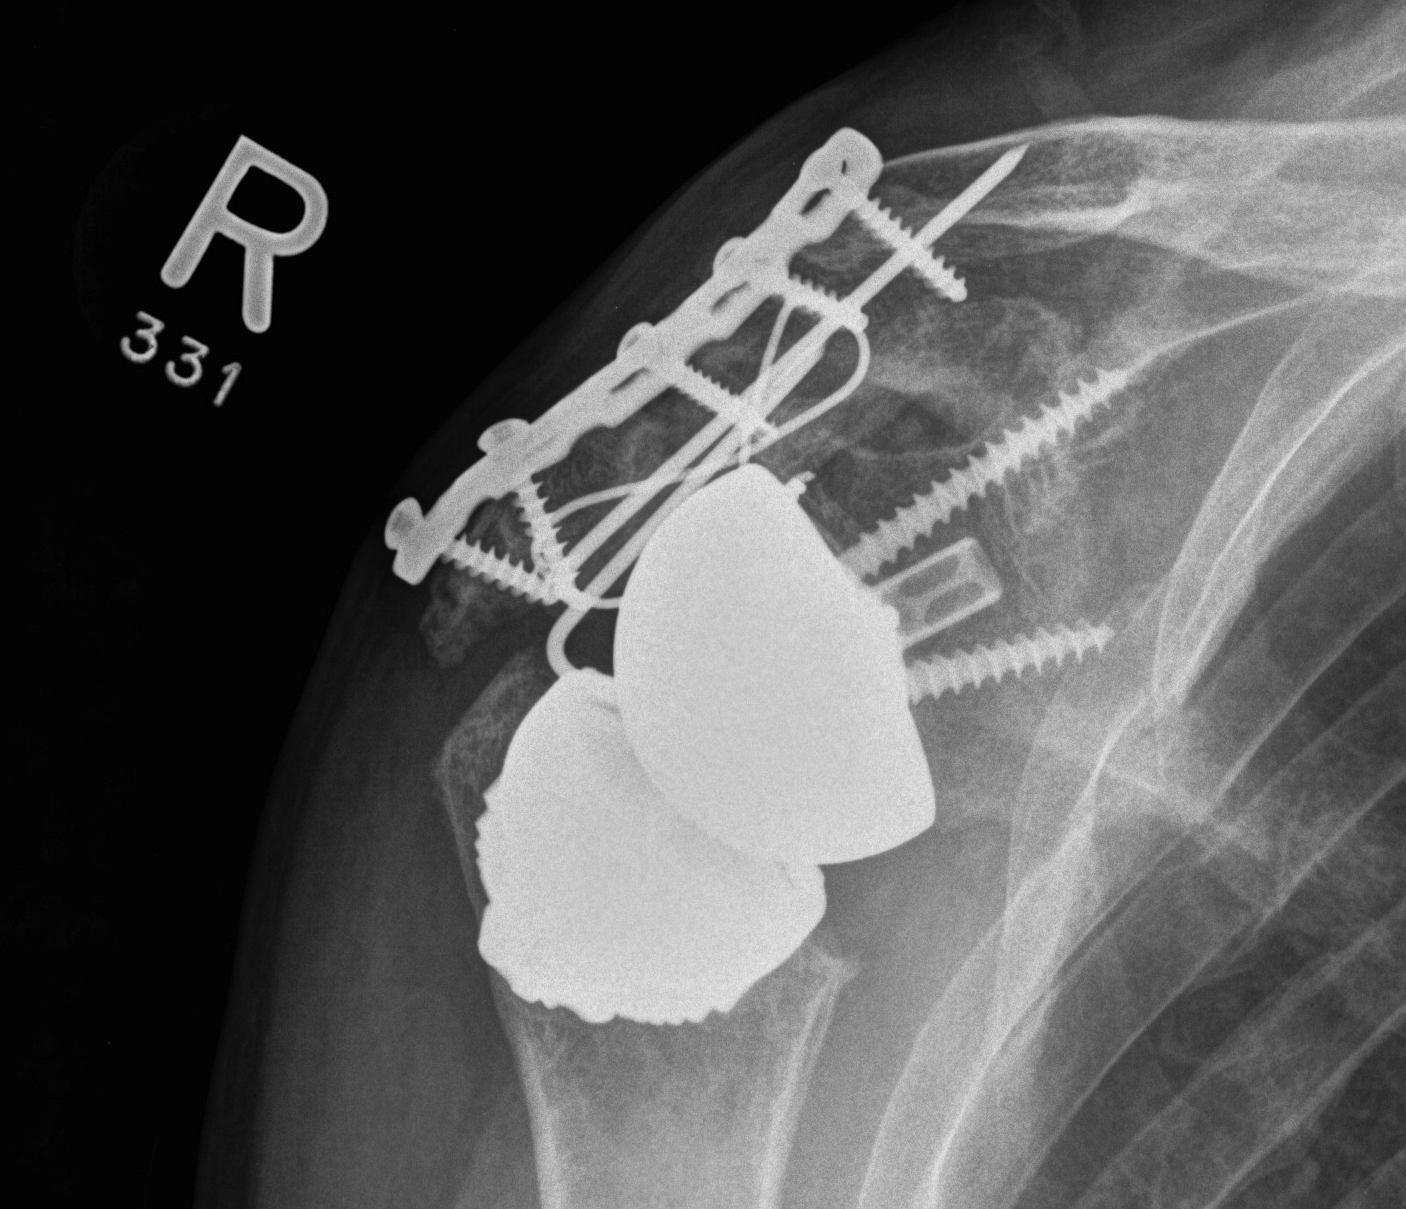

Reverse TSR Acromial Fracture ORIF